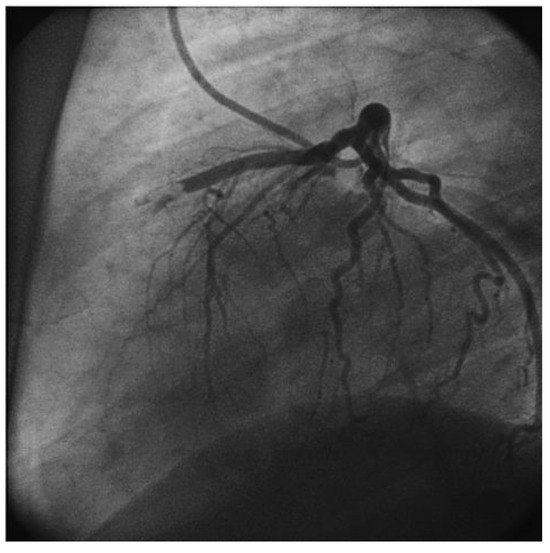

New Amplatzer Duct Occluder II for Antegrade Closure of Patent Ductus Arteriosus

by Stéphane Cook, Tobias Rutz and Bernhard Meier

Cardiovasc. Med. 2009, 12(11), 313; https://doi.org/10.4414/cvm.2009.01457 - 13 Nov 2009

Transcatheter closure of patent ductus arteriosus is a safe and effective technique. The new version of the Amplatzer PDA occluder (Amplatzer Duct Occluder II) permits antegrade delivery and significantly simplifies the procedure. Full article

Show Figures

Figure 1